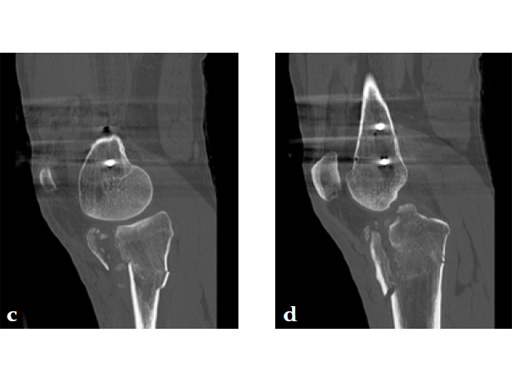

The patient returned to the operating room once soft tissue allowed for open reduction and internal fixation of the tibial plateau fracture via a lateral utility and anteromedial approach. Placement of low bend 3.5 mm proximal tibia plate laterally and 3.5 mm locking T-plate anteromedially to buttress the impacted anterior rim (Fig 4, Fig 5).